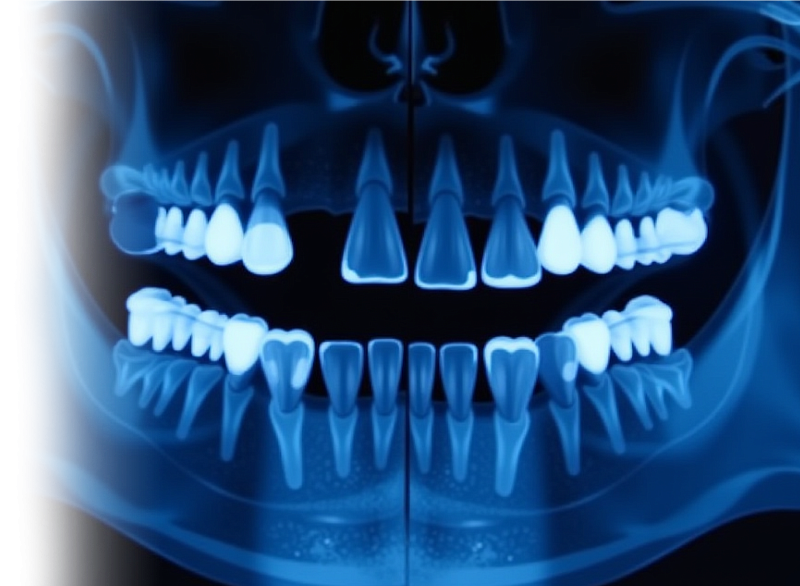

Компьютерная томография челюстей – важный метод прицельного исследования состояния верхней и нижней челюсти.

Для диагностики состояния зубного ряда целесообразно использование КЛКТ.